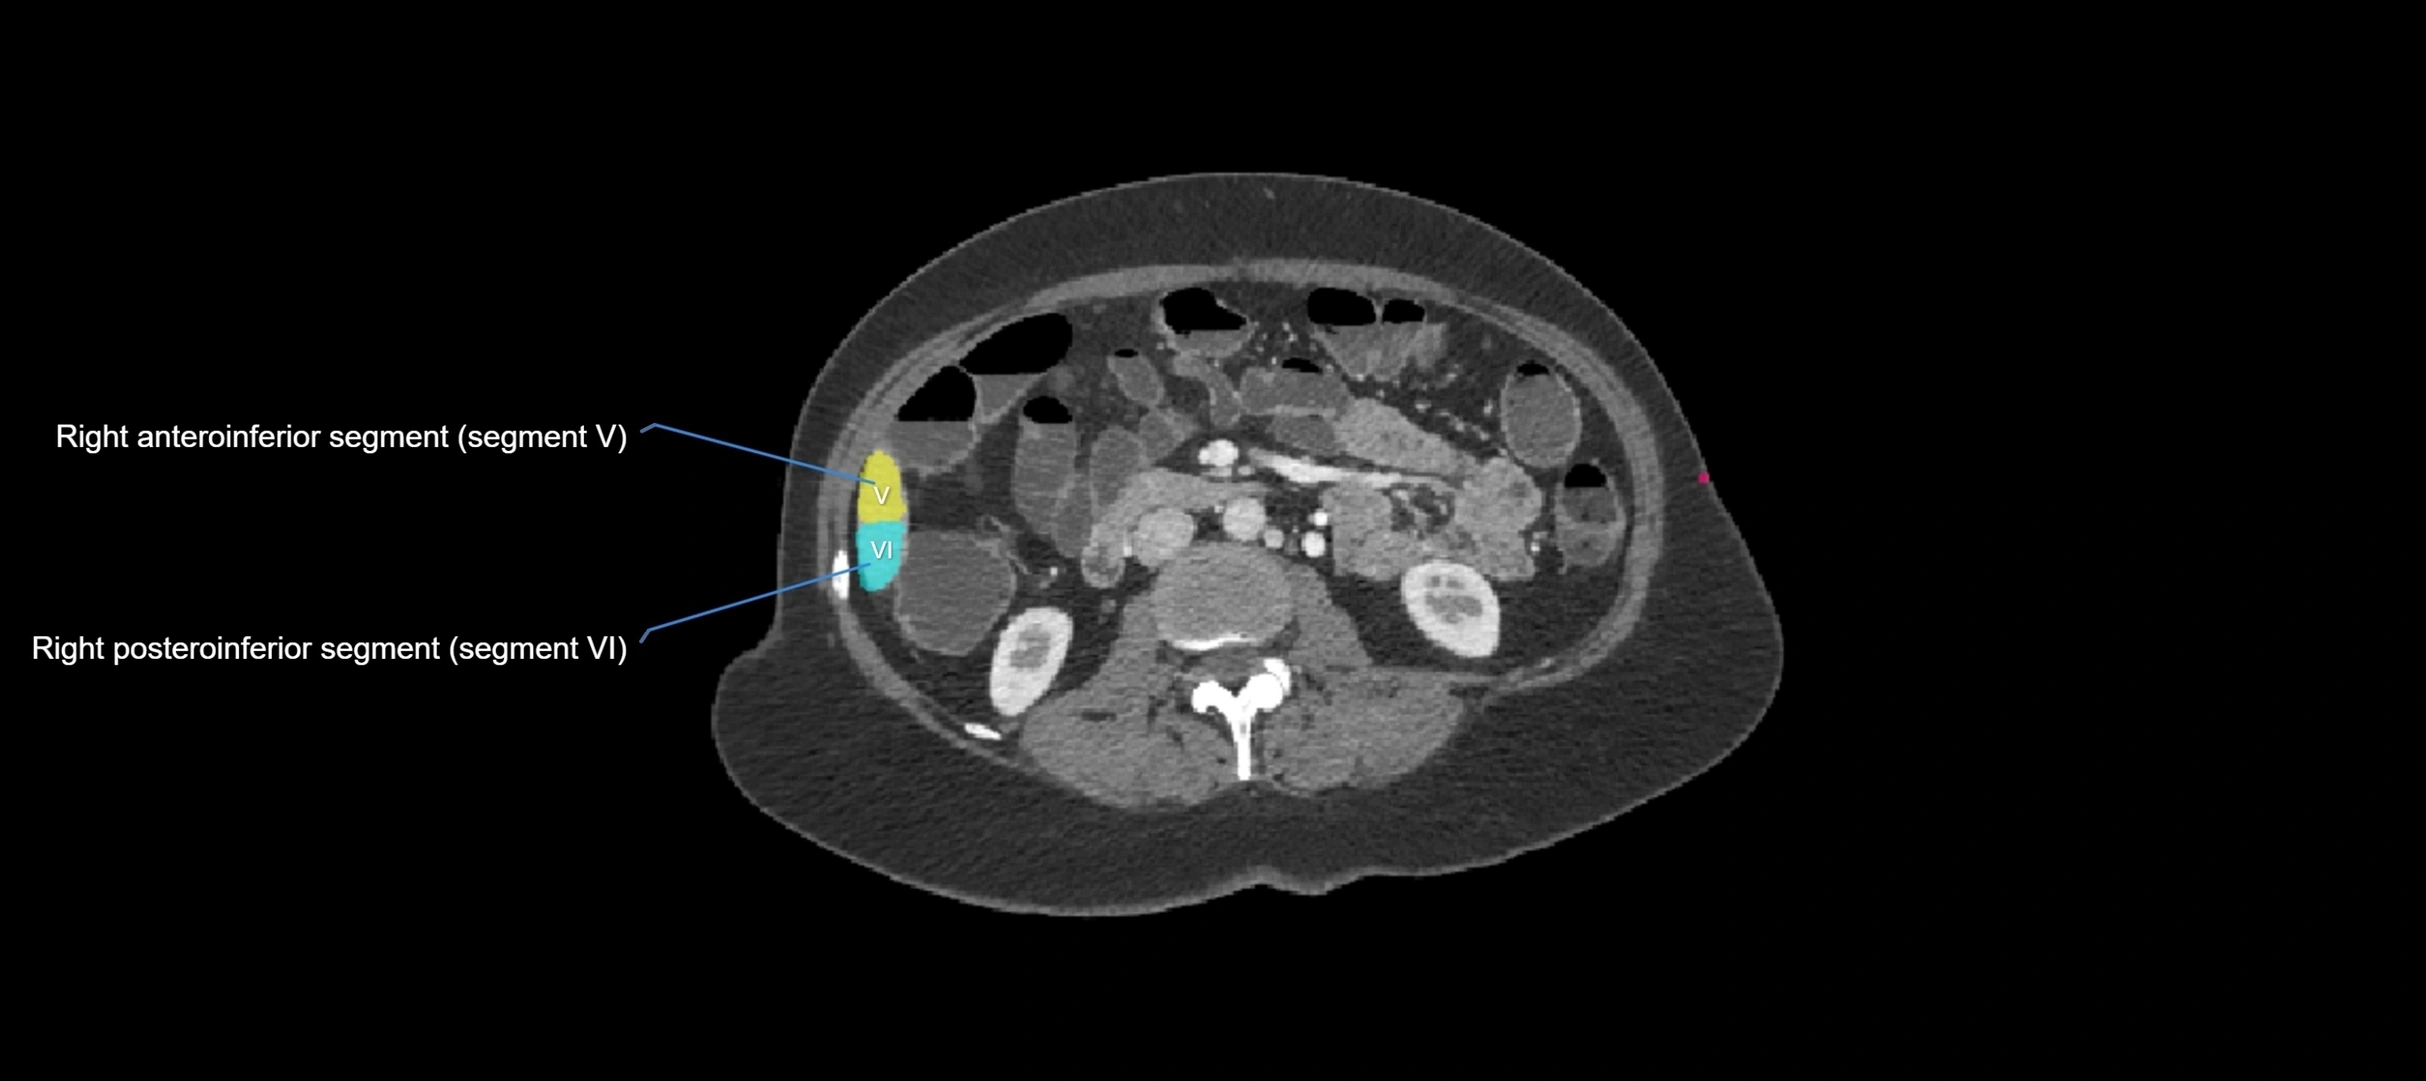

CT Appearance

CT Pre-Contrast:

• Caudate lobe appears as a soft-tissue density, isodense to the rest of the liver

• Enlargement may be appreciated in cirrhosis or Budd–Chiari syndrome

CT Post-Contrast:

• Homogeneous enhancement in the portal venous phase, similar to rest of liver

• Independent venous drainage into the IVC may be visualized

• Lesions follow characteristic CT enhancement patterns (HCC: arterial hyperenhancement with washout; hemangiomas: peripheral nodular enhancement with centripetal fill-in)

CT Image

image